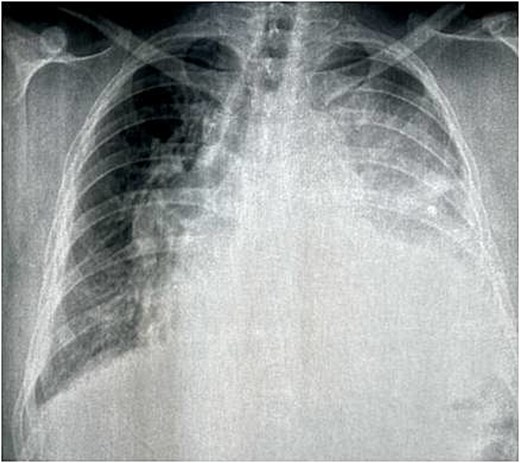

Chest X-ray revealed a left opacity that encompassed the cardiac outline and displaced the trachea and stem bronchi on the right (Fig. 1).

Chest X-ray showed a left opacity that encompassed the cardiac outline and displaced the trachea and stem bronchi on the right.